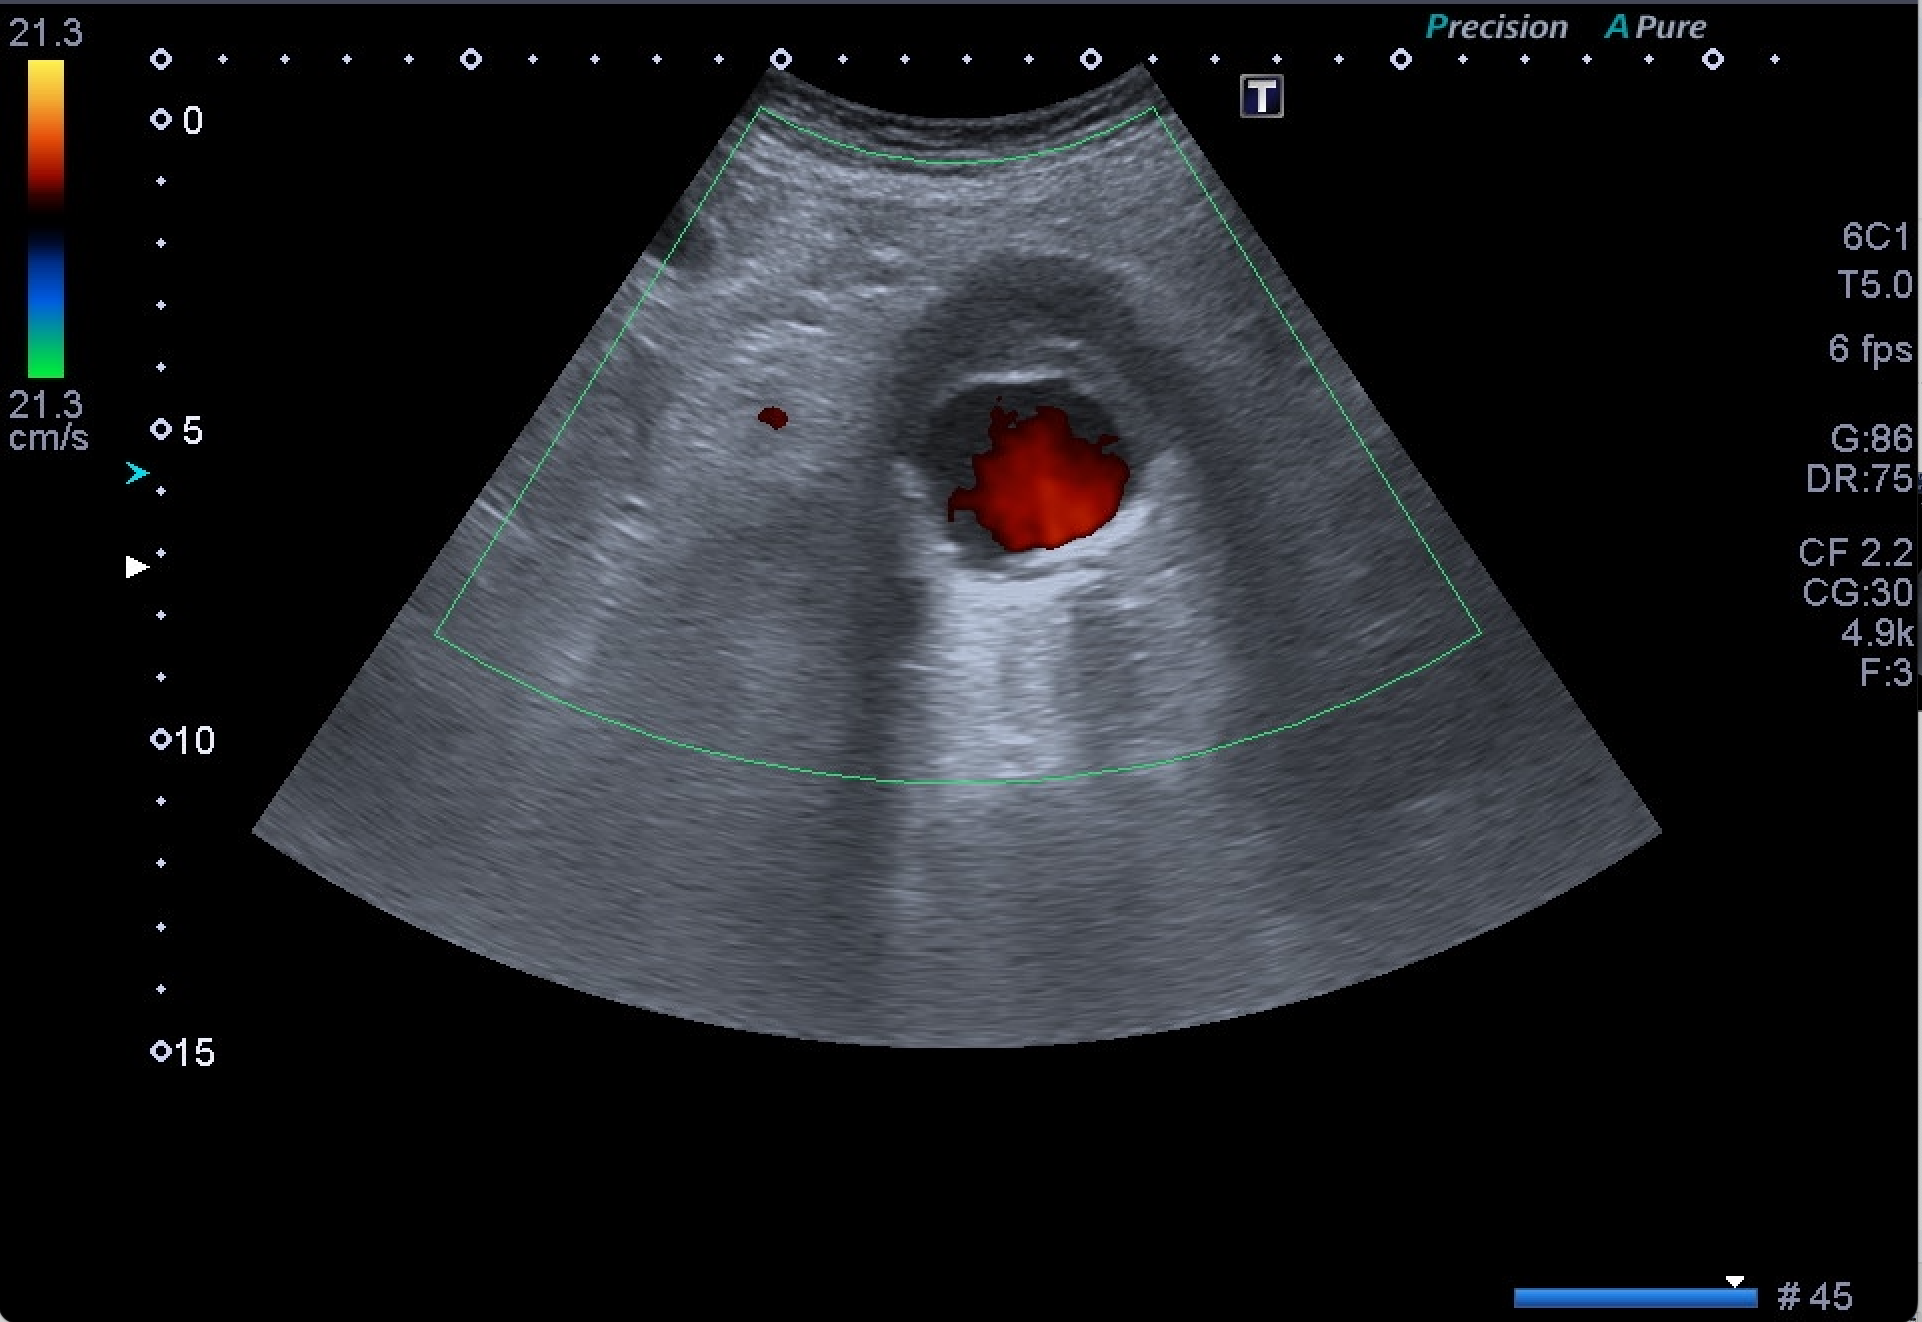

Destaca la visualización de probable litiasis renal derecha, junto con el hallazgo incidental de aneurisma de aorta abdominal, de unos 5,8 cm de diámetro máximo en el plano axial, el cual presenta trombo mural.